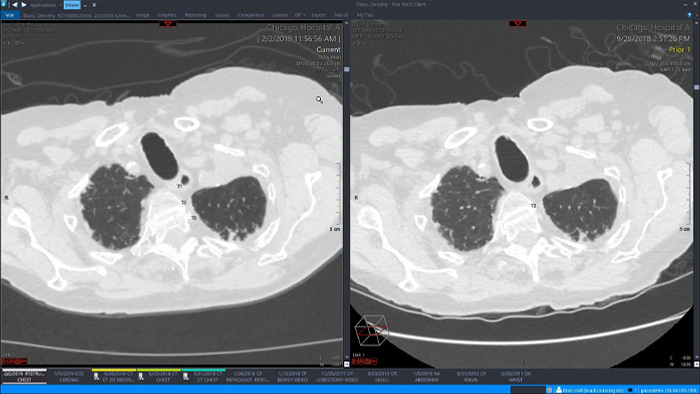

統一された方法のメリットをいくつか見てみましょう。放射線科の単一の統合ワークスペースには、高度な3D後処理機能と画像配信機能が組み込まれており、別のビューアタブで簡単に開くことができます。

統一されたワークスペースでは、ユーザーは複数の臨床分野で利用できる70種類以上の高度なアプリケーションから、関連する解析ツールを簡単に起動できます。人工知能は、タスクとワークフローを自動化して使用パターンを予測する役割を果たします。

エンタープライズイメージングプラットフォームと完全に統合され、診断ビューアに組み込まれたオールインワンのワークスペースでは、臨床分野で必要なすべてのツールに簡単かつ効率的にアクセスできます。バーチャル結腸内視鏡検査、3D処理、スペクトラルイメージングなどの高度な画像解析ツールにワンクリックでアクセスできるため、効率的な解析が可能になり、診断の信頼性が向上します。

AIアシストによる定量的評価と自動結果生成のための強力なツールセットにより、高度な視覚化を実現します。